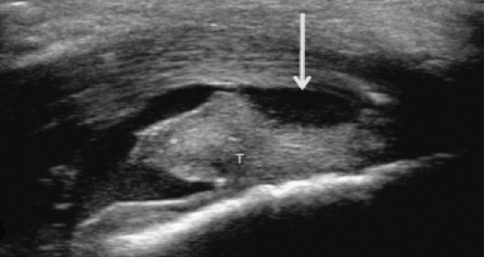

Achados ultrassonográficos na deformidade de Haglund

- Exostose calcânea posterossuperior (a “protuberância”).

- Pode ser visto esporão calcâneo subjacente.

- Espessamento focal na inserção (normal: 4–6 mm; >7–9 mm ou mais sugere patologia).

- Perda da ecotextura fibrilar normal — parece hipoecoico e inchado.

- Tendinopatia insercional e/ou rupturas de espessura parcial.

- Hiperemia ao Doppler na inflamação crônica/ativa.

- Bursa retrocalcânea: Distensão anecoica ou hipoecoica (acúmulo de líquido).

- Bursa superficial/subcutânea: edema hipoecoico entre a pele e o tendão. Ambas as estruturas podem parecer aumentadas e inflamadas.

- Convexidade dos tecidos moles posteriores ao tendão (bursite superficial).

- Interface rompida onde o tendão encontra o calcâneo.

A ultrassonografia é uma modalidade altamente eficaz para avaliar ou diagnosticar a deformidade de Haglund e a síndrome de Haglund, além de auxiliar na definição de patologias ósseas e de tecidos moles ao redor da inserção do calcâneo. Os principais achados incluem uma protuberância calcânea posterossuperior, tendão espessado e hipoecoico, bursite retrocalcânea e superficial e aumento do fluxo Doppler em casos de inflamação ativa.